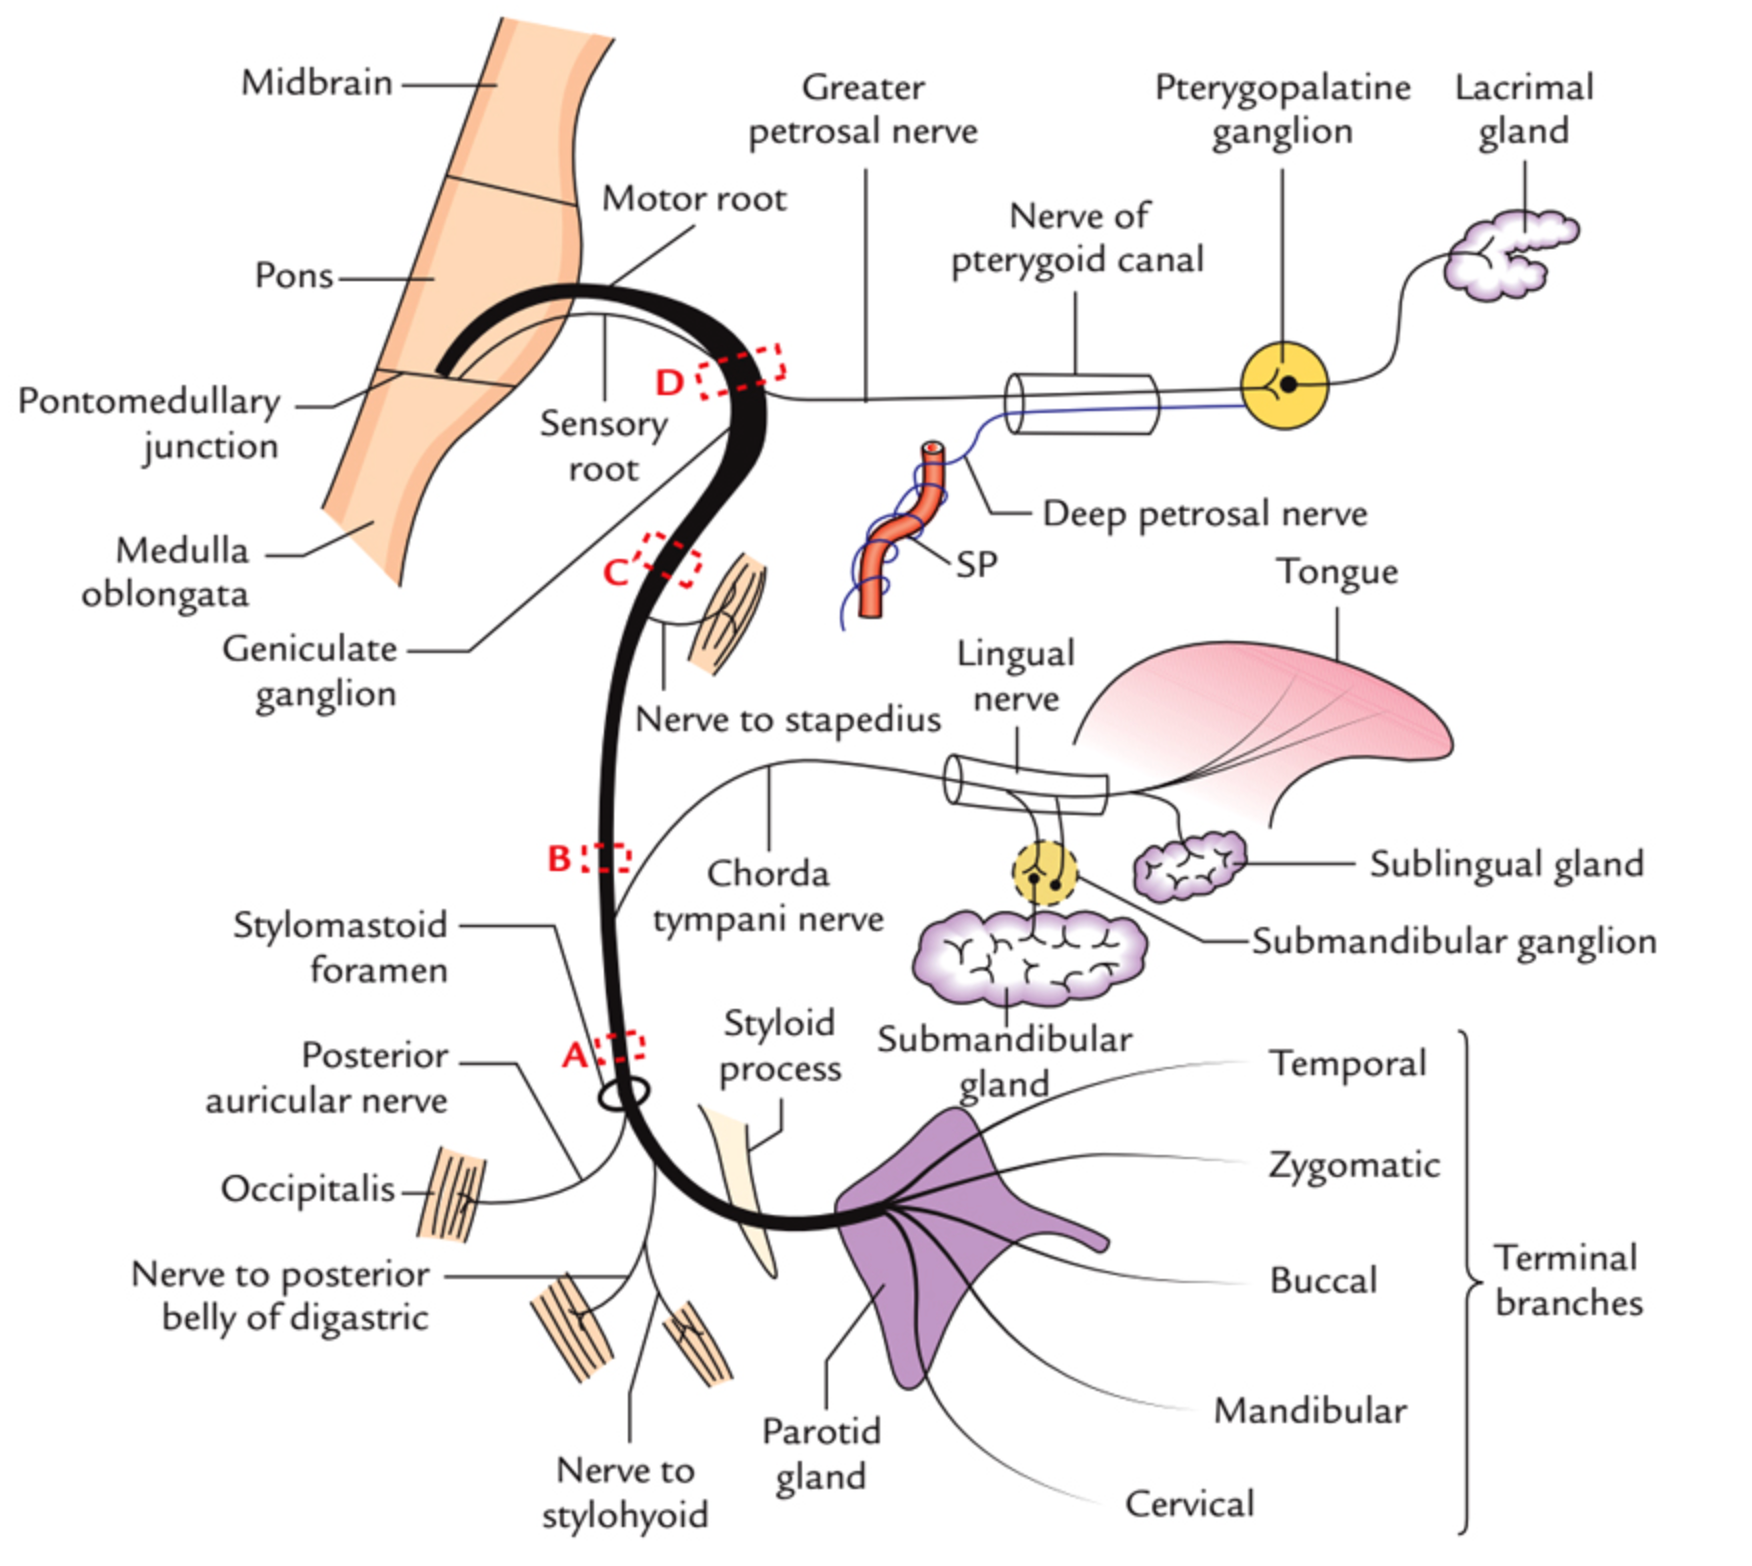

⑦: Sensory; Tast ant ⅔, sound sensitivity | Motor; Eye clos, Mouth close, blow, whistle, smile

- Facial Nerve; Keep eyes closed against resistance, blow cheeks, show teeth

CN VII - Facial Nerve

Course???

in middle ear gives two branches to chorda tympani & Stapedius (ear distrubance)

Innervations - External acoustic meatus - for sensation of ear - Motor - Movement of the face - Sternomastoid - branches nerve to stapedius - Loud sounds middle ear - & nerve to chorda tympani - Parasympathatic Submandibular & Sublingual gland

Tests

- Temporalis - raise eye brows (dont use hands )

- Orbicularis Oculi - check for resistance when eyes close

- Buccinator - Blow (palpate)

- Levator Anguli Superioris - smile

- Orbicularis Oris - whistle

- Taste anterior 2/3

UMN Palsy - Causes Includes; (hyperreflexia)

- stroke

- MS

- trumours

- Internal capsule palsy

- Eyebrow raise is normal - if botox, contraindicated for the test

LMN Palsy - Causes includes

- Bells palsy

- Cavernous sinus thrombosis

- Fracture (truama) base of skull

- Acoustic neuroma

- Shingles

- Ramsay Hunt Syndrome with skin lesioned shingles on face and ear due to varicella ,

- Eyebrow doesn’t raise compared to contra-lateral

Bilateral facial nerve palsy - Sarcoidosis - Guillain-Barré Syndrome - Lyme disease